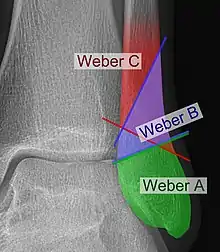

Danis–Weber classification on X-ray.

The Danis–Weber classification (often known just as the Weber classification) is a method of describing ankle fractures. It has three categories:[1]

Type A

Fracture of the fibula distal to the syndesmosis (the connection between the distal ends of the tibia and fibula). Typical features:

Type B

Fracture of the fibula at the level of the syndesmosis. Typical features:

Type C

Fracture of the fibula proximal to the syndesmosis. Typical features: